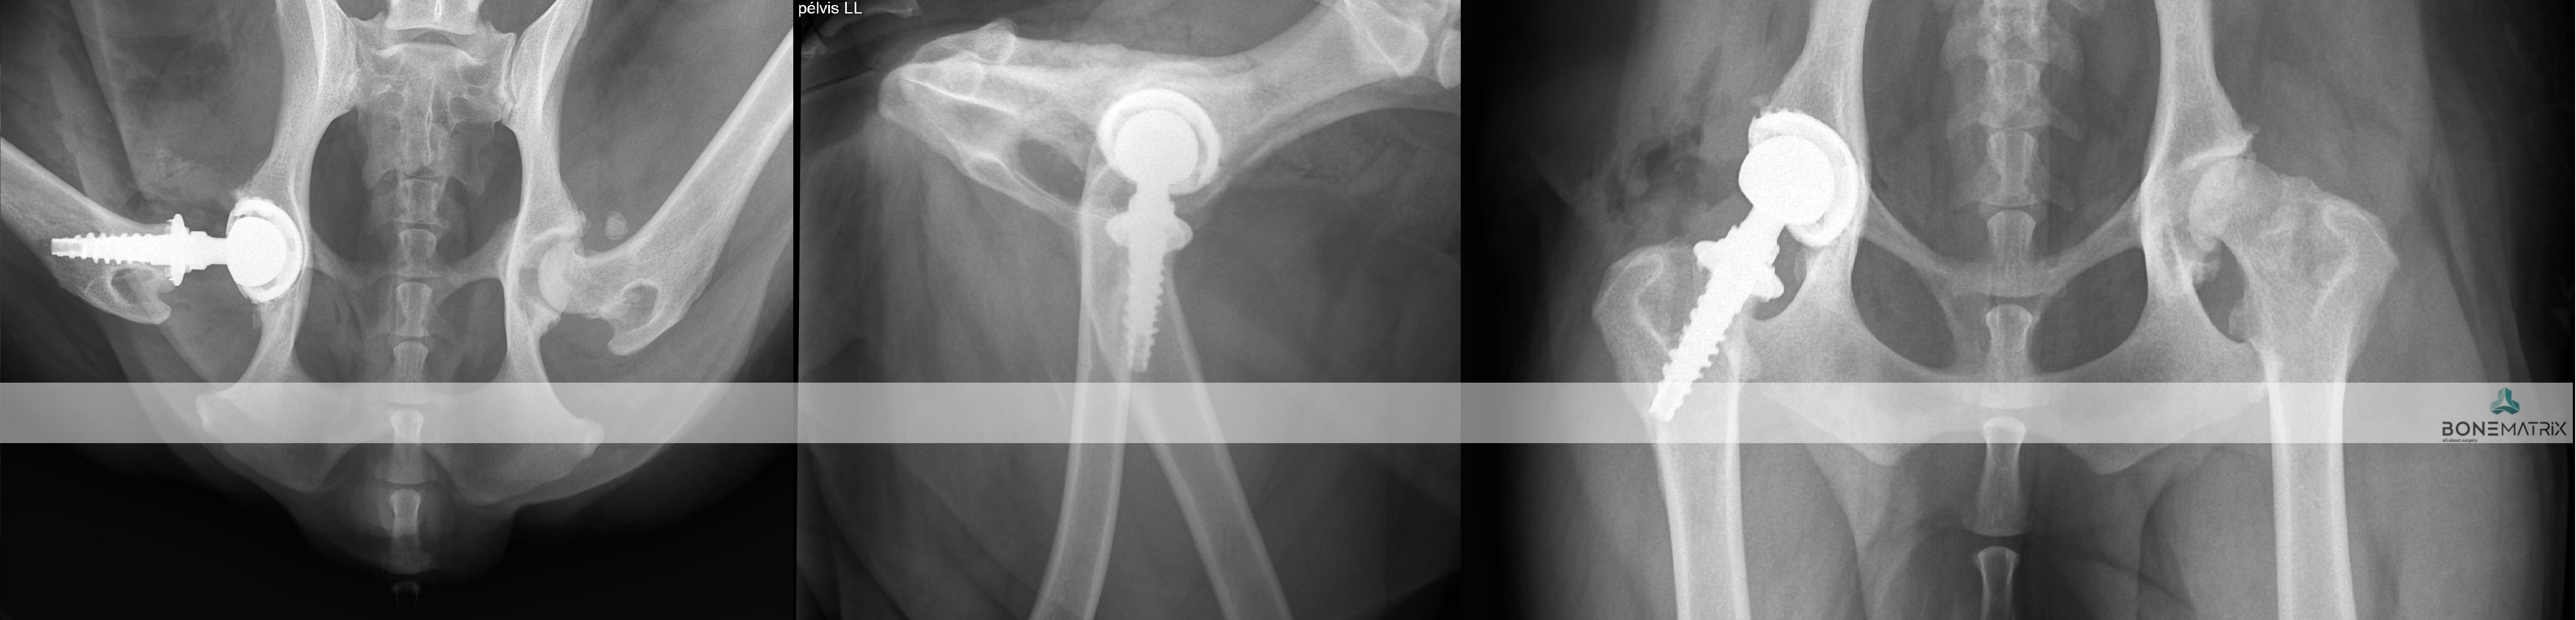

A Prótese Total de Anca (THR - total hip replacement) é um procedimento cirúrgico onde a articulação coxofemoral é completamente substituída por uma nova articulação protésica.

Em medicina humana, esta é a cirurgia de eleição utilizada como tratamento de quadros de osteoartrite severa, apresentando taxas de sucesso extremamente elevadas. Da mesma forma, esta é a solução mais avançada no paciente canino para o tratamento de osteoporose-artrite e displasia de anca, sendo a única capaz de restaurar uma função normal, com normal amplitude e ausência de dor.

Nem todos os pacientes são bons candidatos a THR pelo que os pacientes deverão começar por fazer uma consulta, com estudo radiográfico e avaliação da condição real de cada paciente em particular.

Os pacientes candidatos passam então a uma fase de estudo précirurgico, para que a cirurgia seja planeada com detalhe e se possam escolher a configuração e dimensão de implantes mais adequada.

A cirurgia consiste na eliminação das duas componentes articulares (cabeça femoral e acetábulo) com alterações patológicas e substituição por uma articulação protésica constituída também por duas peças que mimetizam a função da articulação anterior.

Qual a taxa de sucesso esperada?

Esta técnica de uma taxa de sucesso de 95%, sendo a taxa de complicações maiores cerca de 10%.

A restrição de exercício no pós operatório assim como a aplicação de uma boa técnica cirúrgica são fundamentais para o outcome cirúrgico.

Quais complicações podem surgir?

A maioria das complicações acontecem nas primeiras semanas de pós-operatório, daí que seja um período de especial atenção com os cuidados pós operatórios.